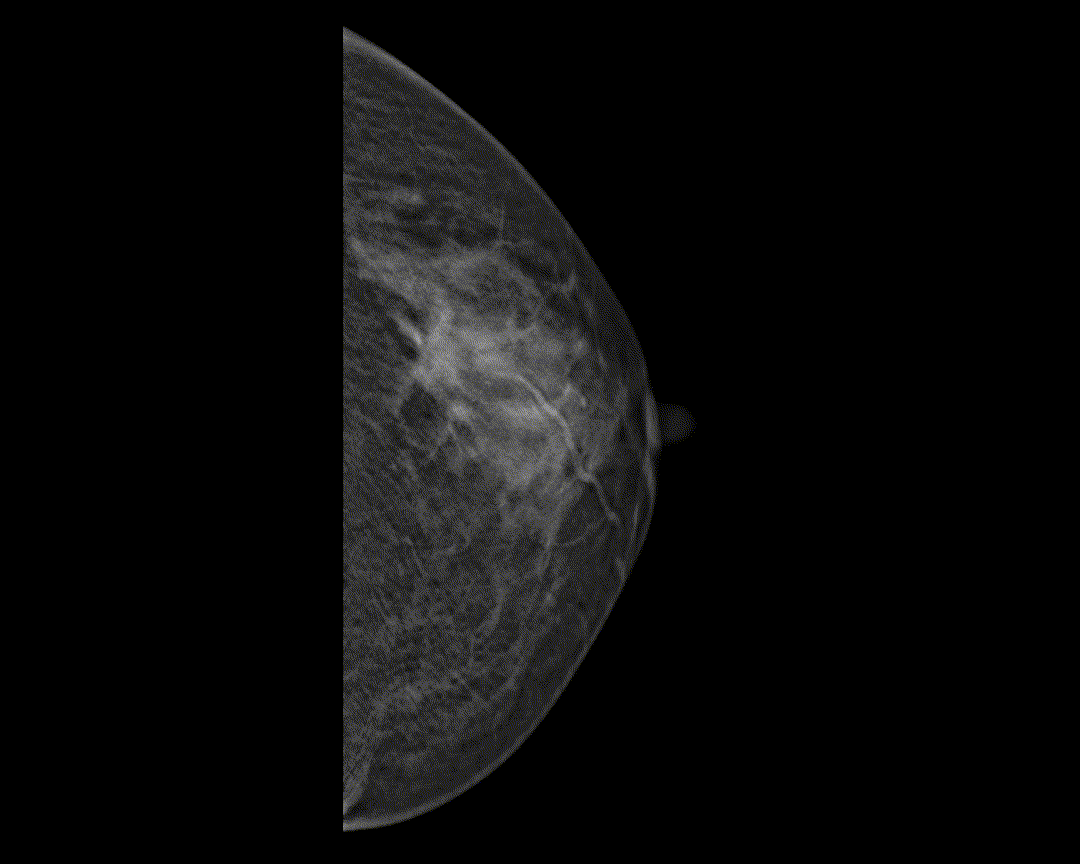

智能乳腺病变分析*

智能辅助病变检测及分析,助力临床诊疗。